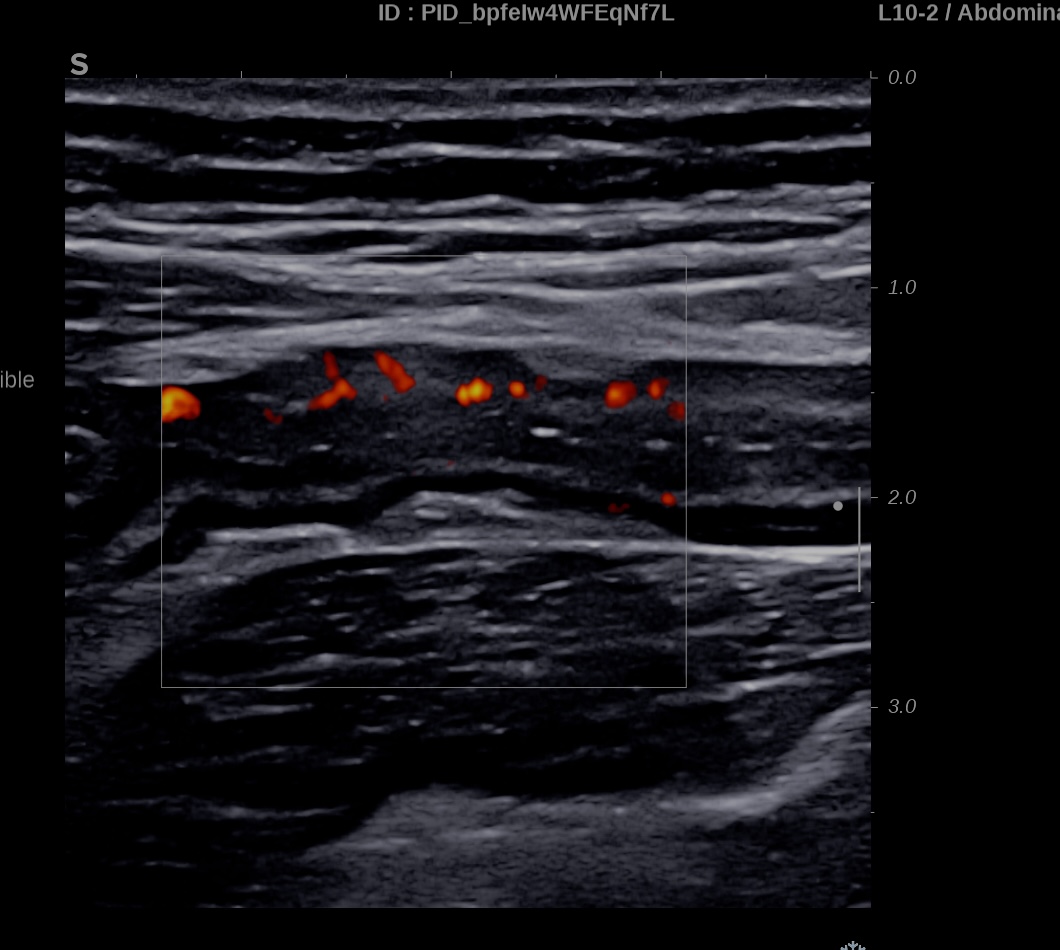

Epaississement considérable par endroit (10 ou 11 mm), disparition totale de la structure en couches, déformation de la surface avec ulcérations, déformation des contours, infiltration de la graisse, hyperactivité Doppler

Le Score de Milan (MUC) est à 17.4

Les images échographiques correspondent parfaitement aux images endoscopiques, et sont finalement beaucoup plus précises que les images scanographiques.